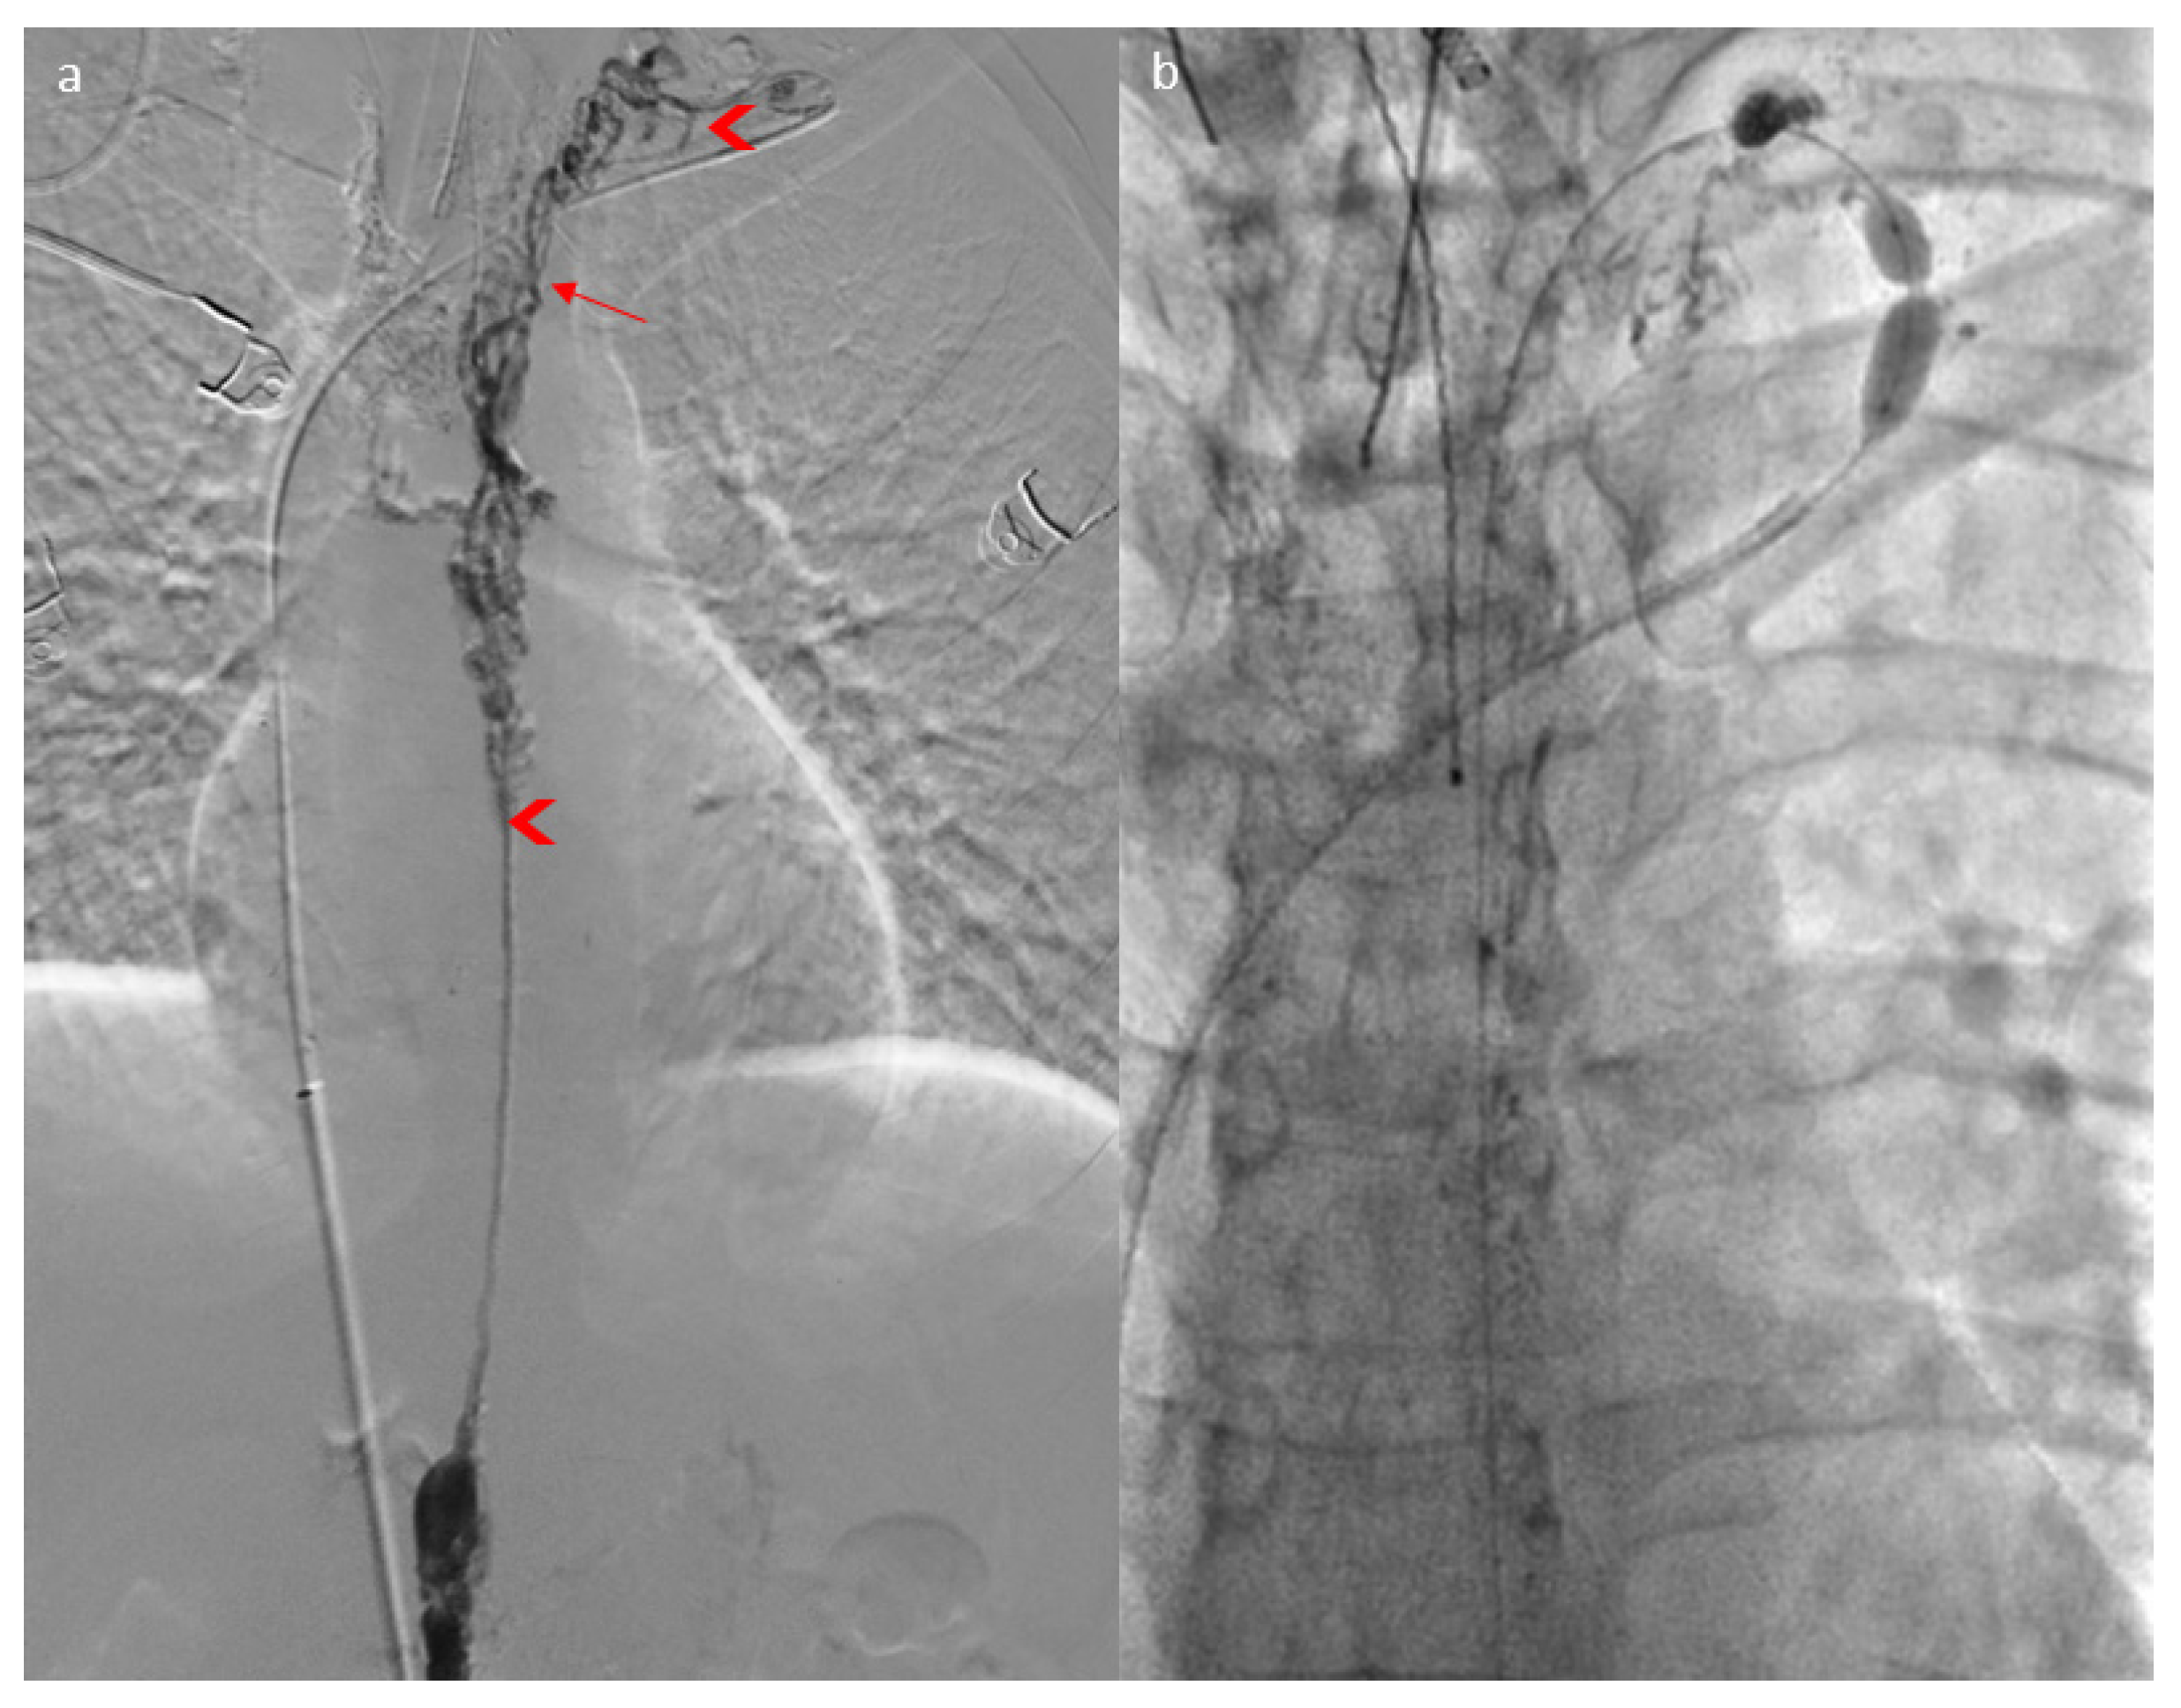

2. Case Report